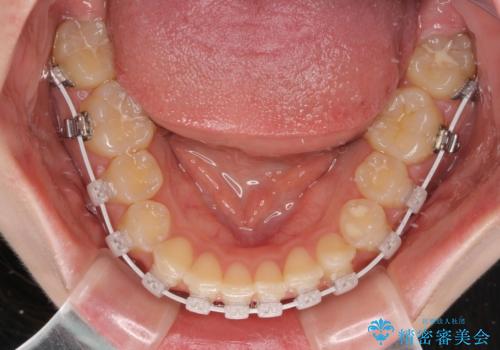

- 審美装置

短期間で確実に仕上げたいとのことで、アンカースクリューと補助装置を併用して歯列の後方移動を図り、ワイヤー装置にて矯正治療を行うこととしました。

左上の歯列は補助装置により速やかに移動し、1年程度で奥歯の咬み合わせが改善され、1年3ヶ月の短期間でしっかりと仕上げることができました。